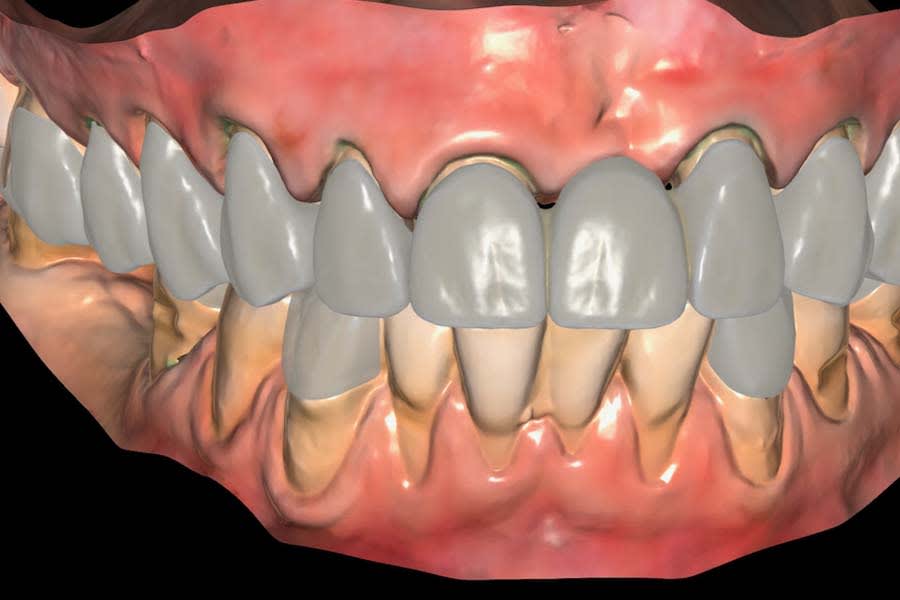

Digital smile design was generated using a biomimetic tooth library in a virtual treatment planning software (Smilecloud 3DNA, Smilecloud, smilecloud.com) and presented to the patient for discussion (Figure 5 and Figure 6). A proposed soft-tissue design that included root coverage procedures and an implant placement option for the replacement of tooth No. 30 was also reviewed. Surgical procedures would be deferred because the patient was planning a relocation within 2 months; however, she expressed interest in pursuing these procedures in the future. Based on the patient’s chief complaint, esthetic goals, and timeline, the treatment plan included replacing the existing FDP and restoring the worn dentition with a combination of CAD/CAM lithium-disilicate partial-coverage indirect restorations and direct composite restorations at a 2 mm increased OVD.